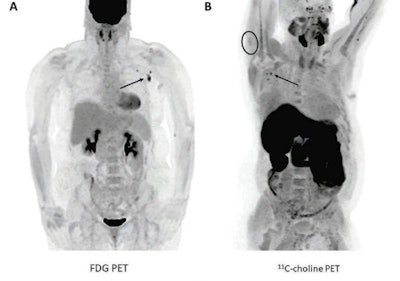

Researchers at the Mayo Clinic in Rochester, MN, compared PET scans of patients before and after they received Pfizer-BioNTech or Moderna COVID-19 vaccinations and observed increased FDG and carbon-11 (C-11) choline uptake by axillary lymph nodes and ipsilateral deltoids. There had been no visible axillary node uptake prior to the vaccinations.

The researchers observed positive axillary lymph node uptake in 10.4% (7/67) of patients on FDG-PET examinations and 23.1% (3/13) of patients who underwent C-11 choline PET imaging. Ipsilateral deltoid uptake was present in 14.5% (8/55) of patients with documented injection laterality, including in 42.9% (3/7) of patients with positive axillary lymph nodes.